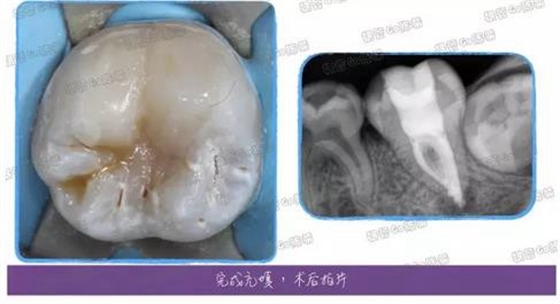

兩周復(fù)診后,疼痛消除,無(wú)其他癥狀,就使用AH根充糊劑+0430及修整后的0625牙膠尖配合熱牙膠充填了,充填完以后覺(jué)得這個(gè)C型很明顯,又用內(nèi)窺鏡拍了一下。

咱們的小主角牙列不齊,媽媽猶豫不決是否做正畸,但是這顆牙現(xiàn)階段咬合也不正常,所以還是選擇直接樹(shù)脂充填,接下來(lái)咱們就進(jìn)入樹(shù)脂充填的階段吧。

使用流體樹(shù)脂封閉根管口以后,復(fù)合樹(shù)脂分層充填,每一層都不要太厚,最好V型充填,然后再一個(gè)個(gè)堆塑牙尖喲~

完成樹(shù)脂充填后,右邊那條頭發(fā)絲樣的東西最開(kāi)始以為是電腦屏幕有頭發(fā),擦了半天沒(méi)擦掉,估計(jì)是反光板拍照時(shí)落下的了。樹(shù)脂的塑形一直做得不好,這例算是稍微好點(diǎn)的了,所以拿出來(lái)請(qǐng)大家指教指教~

堆塑完成后再拍個(gè)根尖片檢查檢查~